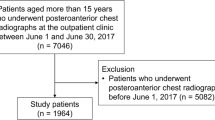

Collection of clinical data used for performance assessment

A total of 411 consecutive patients underwent both chest radiography and chest computed tomography (CT) in September 2019 at a tertiary ED in South Korea, which had more than 100,000 annual visits. For simulation, patient data were extracted from electronic medical records. Images from 23 patients that did not involve any of the three targets (lung nodule, consolidation, and pneumothorax) of DLCR used in this study were excluded. Finally, the clinical data from a total of 388 patients were used for performance assessment. These data were automatically collected through the clinical research analysis portal developed by our medical information department.